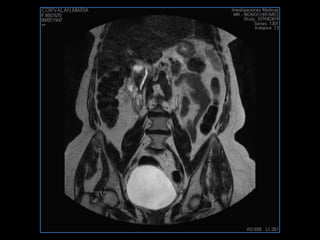

PROTOCOLO pelvis SAG T2, Y FAT SAT (FINOS) AXIAL T1  AX FAT SAT CON   GADOLINIO :  AX T1 Y COR T1 SAT: NO  FASE: RL THK: 3MM  COIL:  GAP: (FACTOR 1.4) 1MM FOV: 40 CM NEX:2 SINCRONIZACION RESPIRATORIA EN 3 O 4 CICLOS ALE